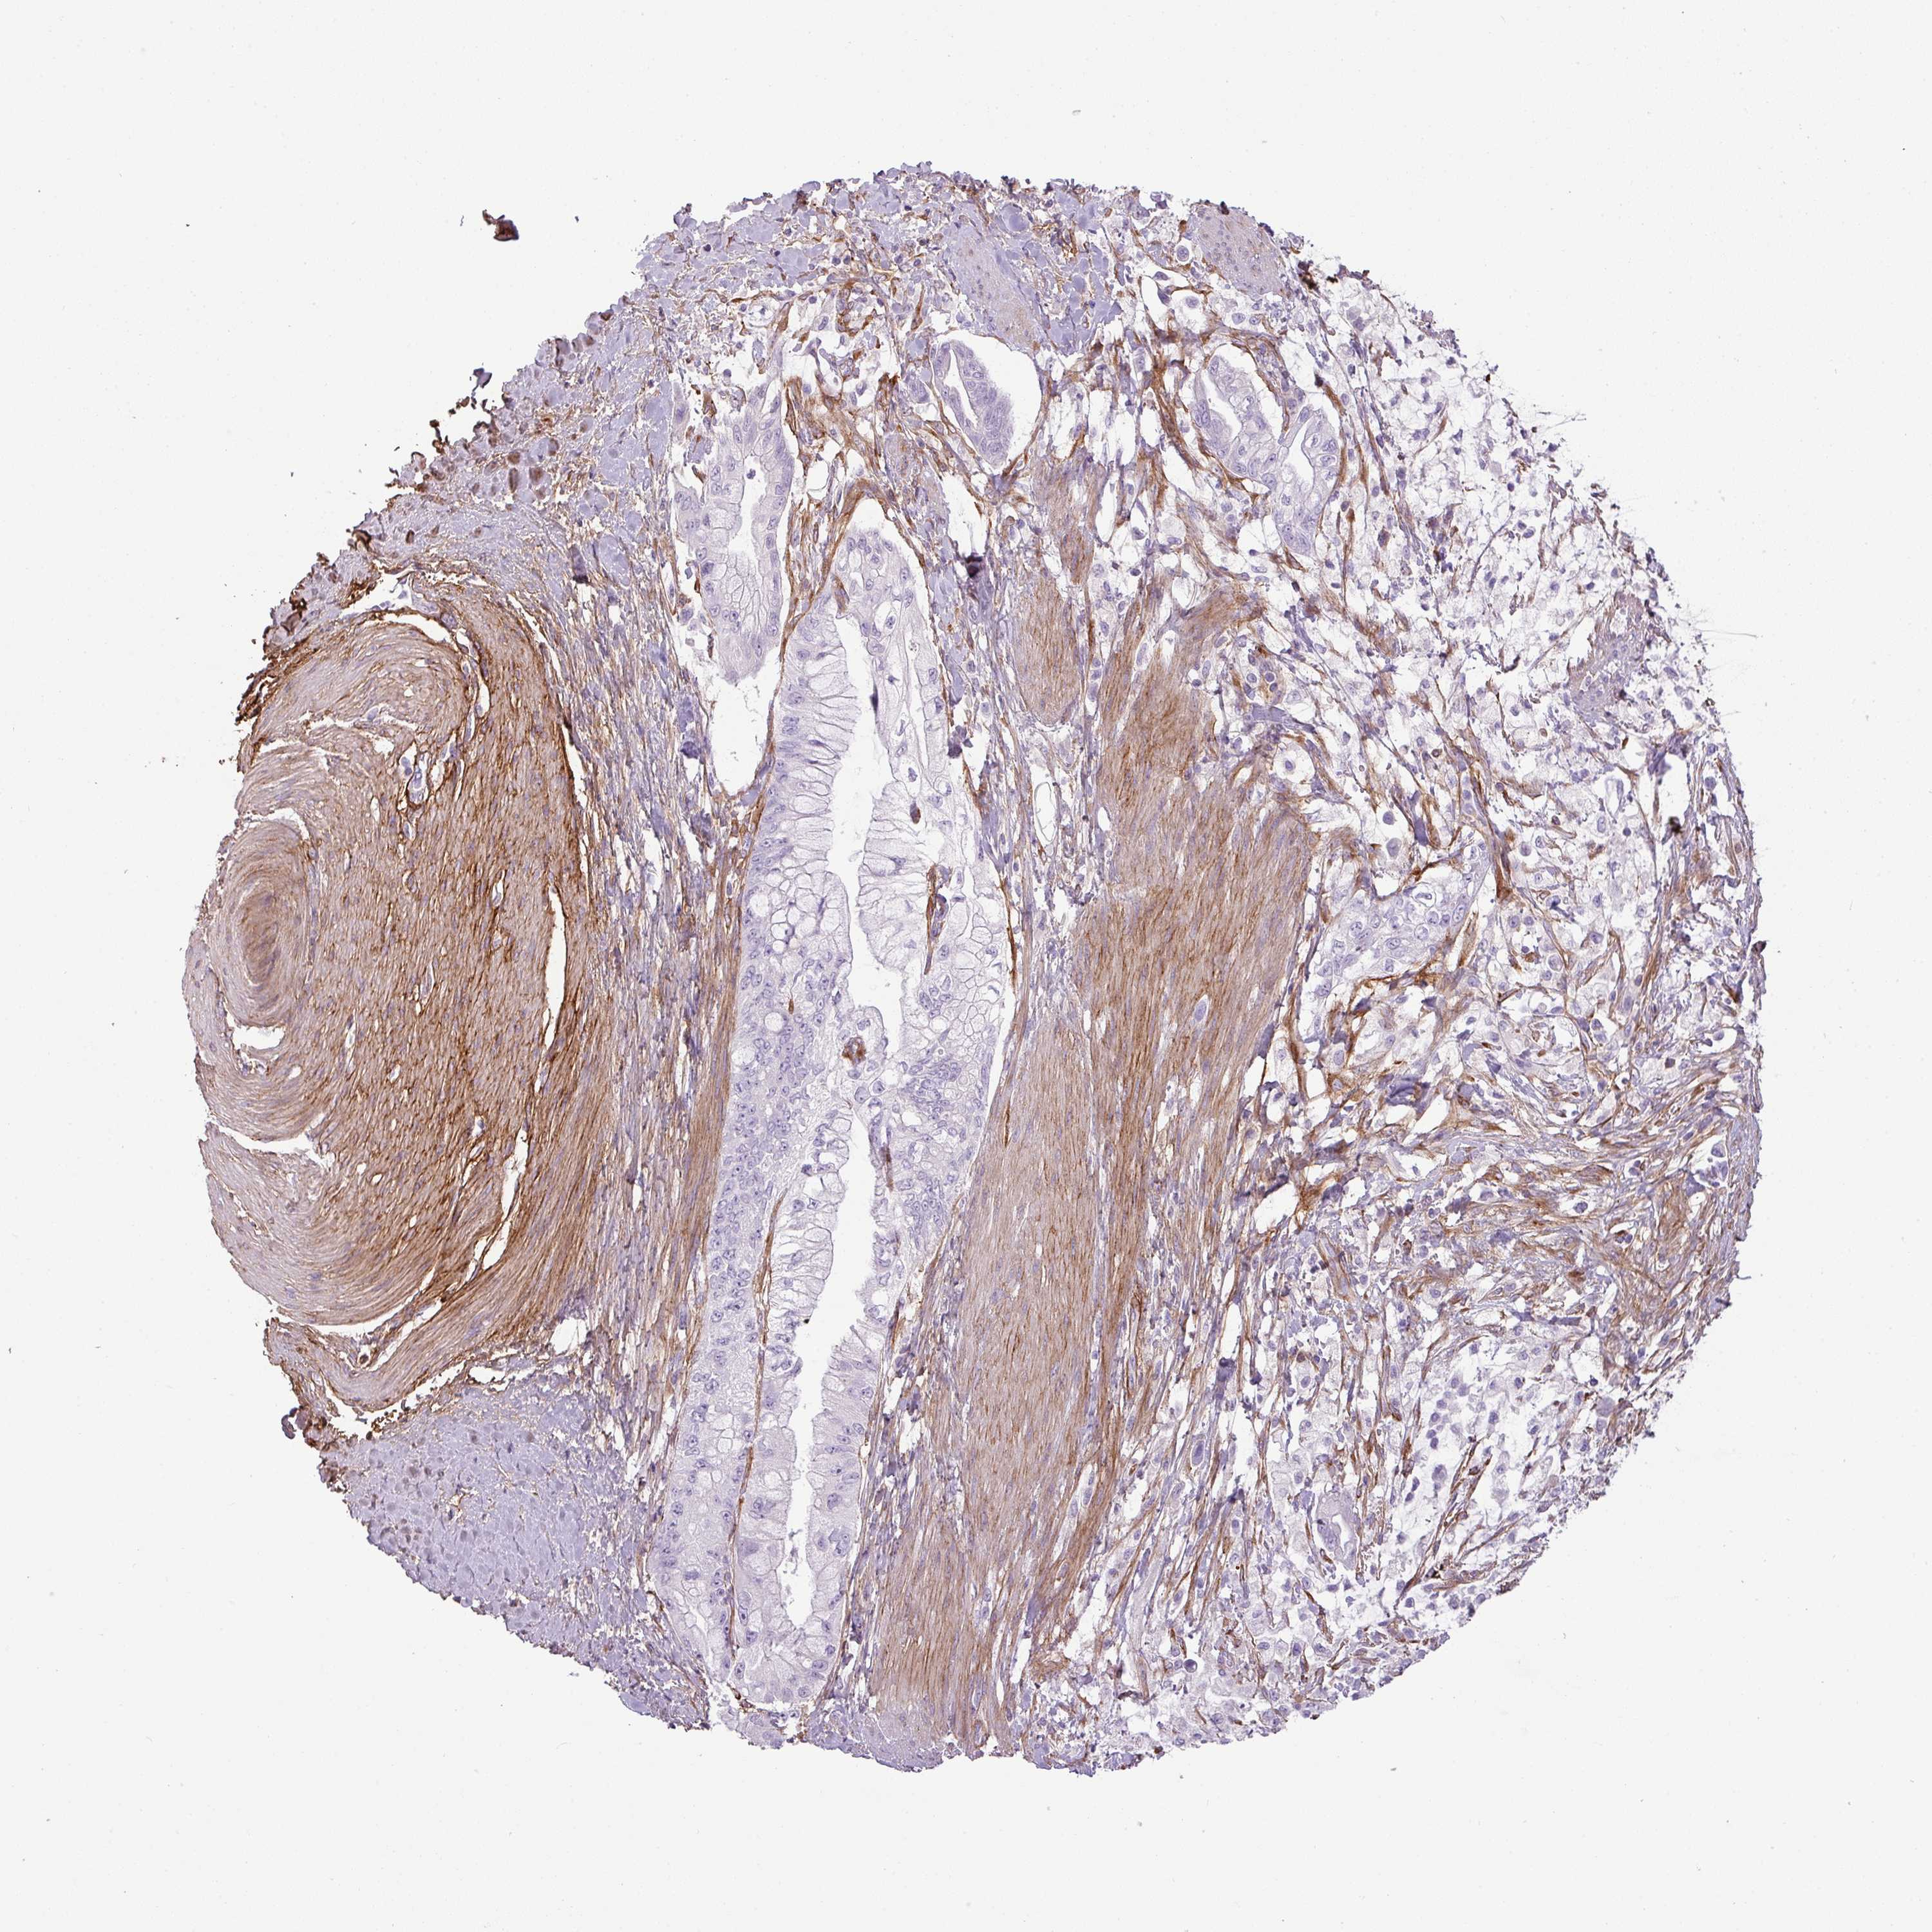

PANCREATIC CANCER - Protein expressioni

A mouse-over function shows sample information and annotation data. Click on an image to view it in a full screen mode. Samples can be filtered based on level of antibody staining by selecting one or several of the following categories: high, medium, low and not detected. The assay and annotation is described here.

Note that samples used for immunohistochemistry by the Human Protein Atlas do not correspond to samples in the TCGA dataset.

Antibody stainingi

Antibody staining in the annotated cell types in the current human tissue is reported as not detected, low, medium, or high, based on conventional immunohistochemistry profiling in selected tissues. This score is based on the combination of the staining intensity and fraction of stained cells.

Each image is clickable and will lead to virtual microscopy that enables deeper exploration of all samples and also displays staining intensity scores, fraction scores and subcellular localization as well as patient and tissue information for each sample.

Antibody HPA047017

Staining

High

Medium

Low

Not detected

Intensity

Strong

Moderate

Weak

Negative

Quantity

>75%

75%-25%

<25%

None

Location

Nuclear

Cytoplasmic/membranous

Cytoplasmic/membranous,nuclear

Adenocarcinoma, NOS